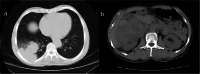

Renal cell carcinomas are known to produce widespread and unpredictable metastasis due to their angioinvasive property. Cutaneous metastases from renal cell carcinomas are very rare, with a reported incidence of 1.3-3%. The sites of cutaneous metastasis from renal cell carcinomas, as per the available case reports, to the best of our knowledge, are shoulder, arm, nape of the neck, chest, face and scalp. We report a case of 63-year-old male, with renal clear cell carcinoma with lung metastasis who had cutaneous metastasis to the fingertip which was confirmed by histopathological examination. Apart from its rarity, this clinical case adds another site of renal cell carcinoma metastasis to the present literature. The skin metastasis represents a widely disseminated state of the disease with a very guarded prognosis and limited life span after its diagnosis.